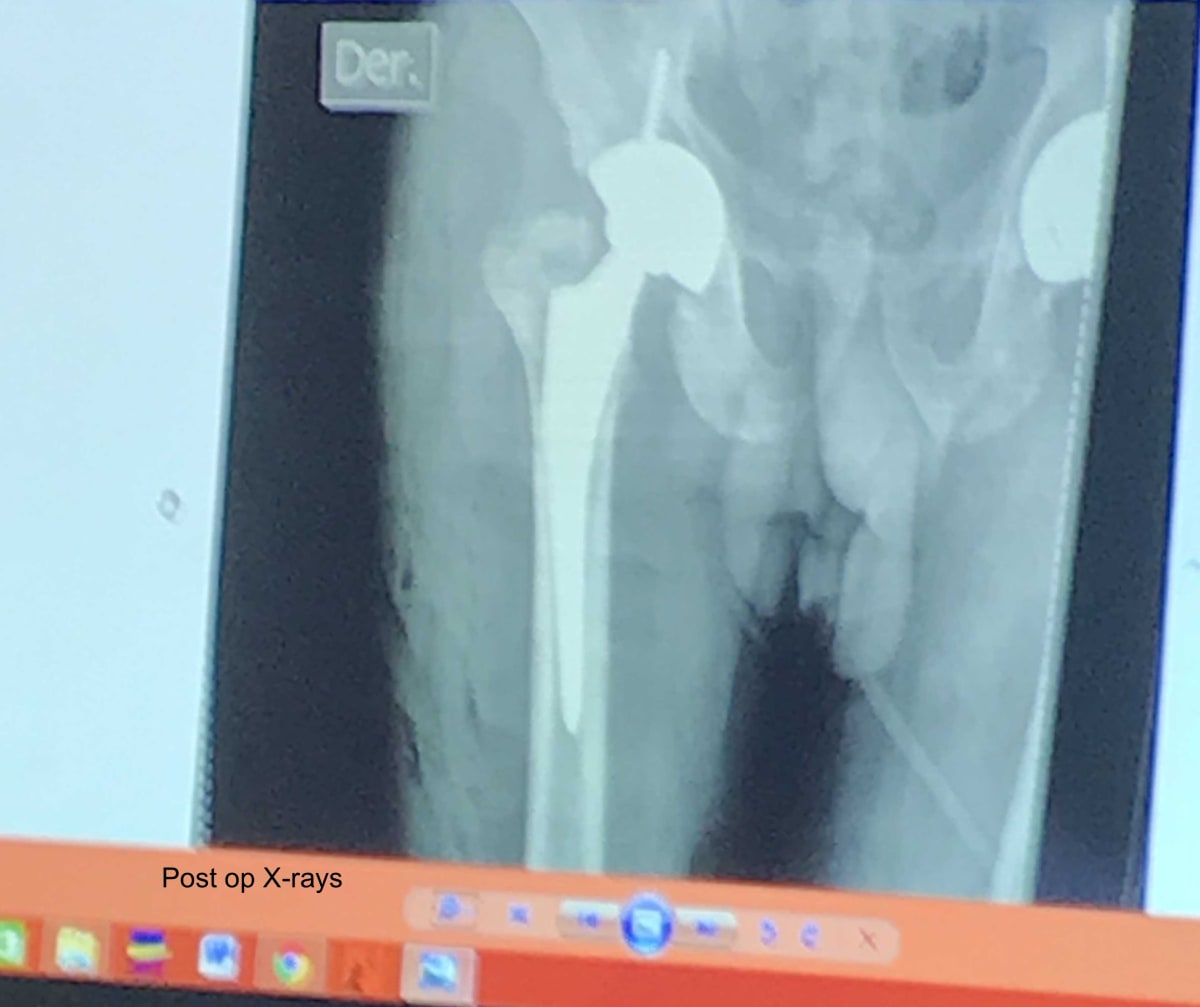

I went to Nicaragua to share knowledge and experience, especially in regards to total joint replacement. This was my first medical mission trip, and I knew there would be logistical challenges with performing total joint surgery. As it turned out, I only got to do one total hip replacement while I was there. However, I was able to scrub several trauma cases with the residents. I also lectured on total hip complications.